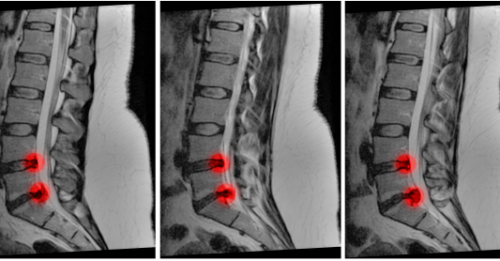

Learn to Spot and Treat Cauda Equina Syndrome

The Case A 58-year-old male presents with worsening lower back pain. He has a history of L4/L5…